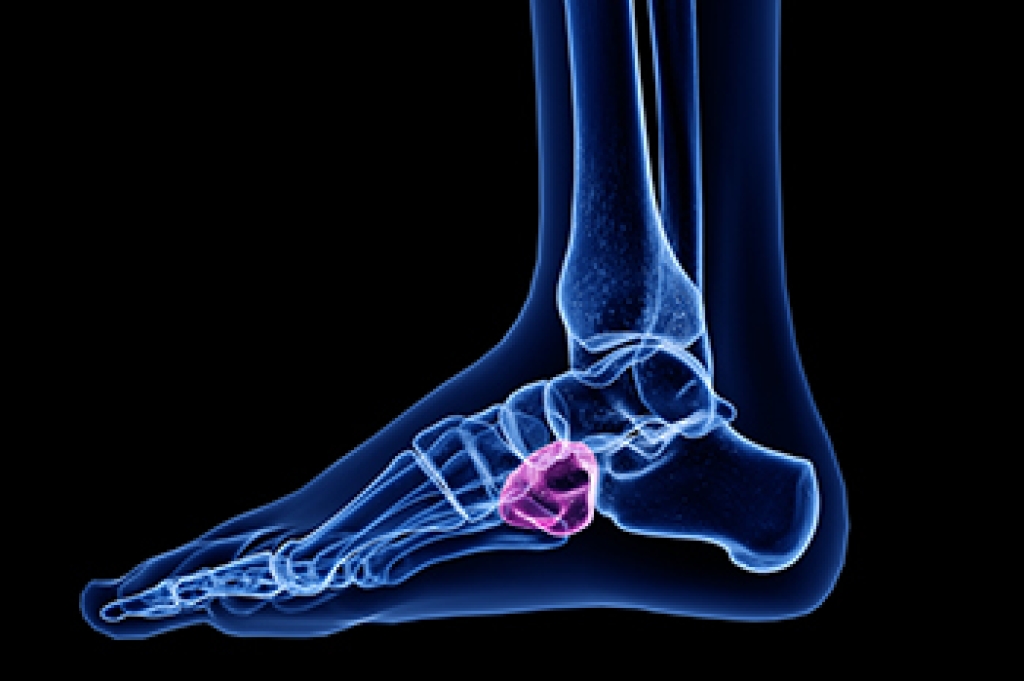

Vincent Vess, DPM is an experienced and compassionate podiatric physician and surgeon. He offers effective, non-surgical treatments for everything from heel pain, ingrown toenails, warts, and diabetic foot issues, to surgical procedures for bunion and hammertoe correction, tendon repairs, neuromas, joint issues, severe plantar fasciitis, sports injuries and more.

Dr. Vess is also a wound care expert. He provides advanced wound care treatments both in his office, and at nearby UPMC McKeesport Wound Center where he is on staff. Additionally, Dr. Vess has a keen interest in biomechanics of the lower extremities. He heals many athletes and runners using various therapies and procedures, surgery when necessary, and custom fabricated orthotic devices.